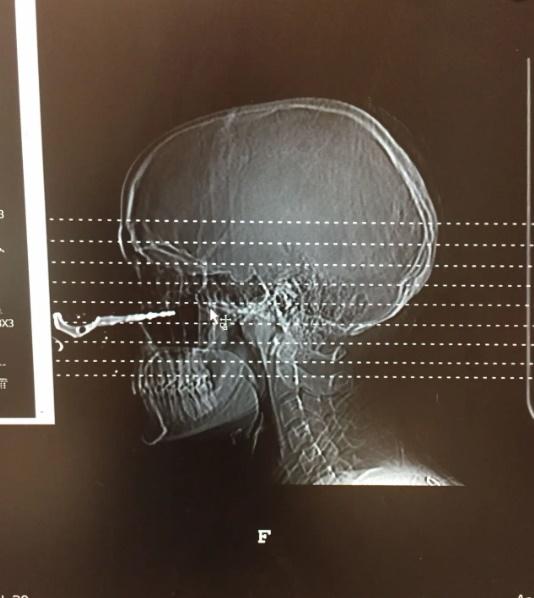

《紐約郵報》(New York Post)報道,事故發生於上月, 24歲女子Renée Lariviere正準備跟朋友出門吃晚餐,當時她的朋友將車匙丟給她,她沒多想就轉身伸手去接,詎料車匙就直插進她的臉頰。

Renée Lariviere指,當下應該是腎上腺素的關係,只覺面被打一下,沒有覺得很痛,但見在場的朋友都驚慌得亂作一團,緊張地著她不要亂動,並致電119求救,她走進廁所查看傷勢,才被鏡中的畫面嚇了一跳。Renée Lariviere說,當時完全無考慮毀容的問題,只擔心自己會否失明。

Renée Lariviere的傷勢在醫院也引起一陣騷動,雖然急症室的醫生們都身經百戰,不過這種傷勢及意外原因實在太離奇,就連其他科的醫生都趕來一睹這「奇景」,更有醫生要求拍照。